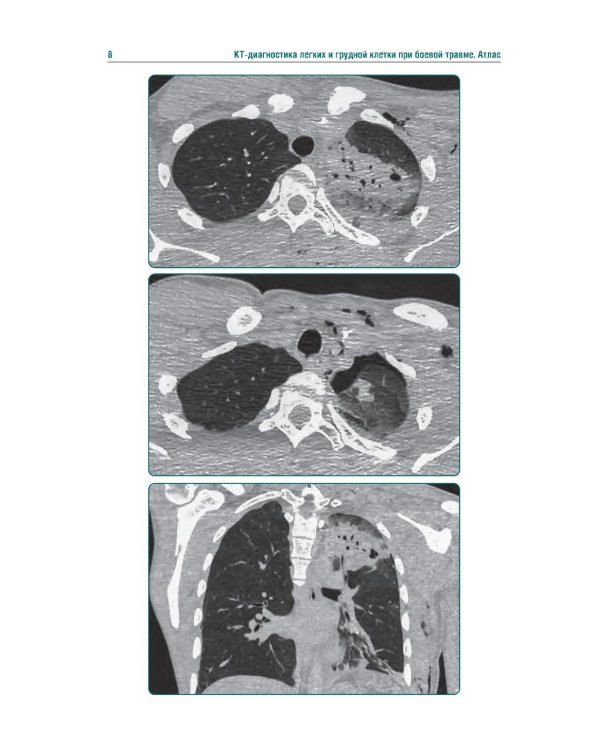

Аннотация: КТ-признаки поражения легких и грудной клетки при боевой травме: атлас

Издание представляет собой первый в Российской Федерации атлас, иллюстрирующий различные виды поражения легких, плевры и других структур грудной клетки у пациентов с боевыми ранениями. В современных условиях количество таких пациентов увеличивается, поэтому существенно возрастает значимость различных видов боевых травм, в том числе повреждений грудной клетки. В атласе представлены уникальные КТ-изображения различных видов боевой травмы грудной клетки, полученных в условиях современных вооруженных конфликтов. Помимо описания характера, условий получения травмы и выявленных повреждений, есть возможность просмотра изображений в формате DICOM. Атлас предназначен для врачей-рентгенологов, торакальных хирургов, пульмонологов, а также врачей других специальностей, занимающихся диагностикой и лечением пациентов с боевыми травмами.| Издательство | ГЭОТАР-Медиа |